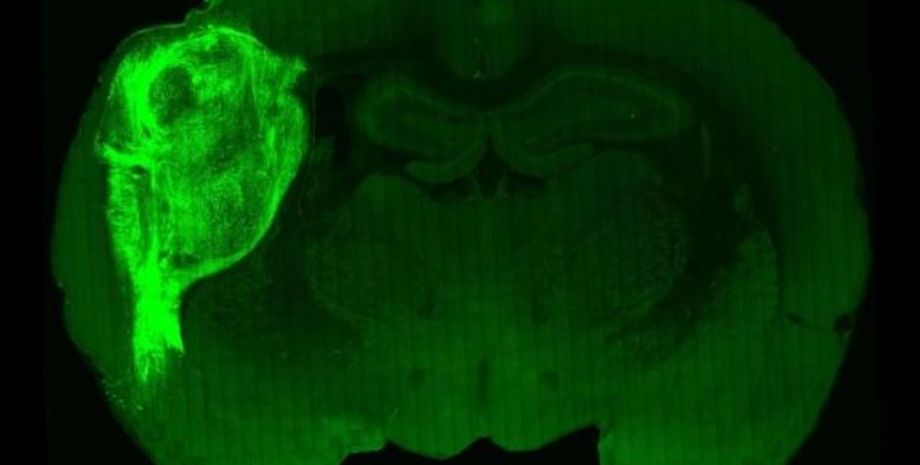

Ткани человеческого мозга успешно прижилысь. | Фото: Stanford University

В результате Пашка с коллегами пересадили ткани человеческого мозга в мозг новорожденных крыс, чей собственный мозг еще не развился и не созрел. Органоиды были имплантированы в соматосенсорную кору, область отвечает за обработку и получение сенсорной информации.

В ходе исследования ученые генетически сконструировали органоиды, чтобы они реагировали на симуляцию синего света, активируя нейроны. Эта стимуляция нейронов проводилась в эксперименте, когда крыс обучали облизывать нос для получения воды. Позже ученые обнаружили, что когда крысы освещались синим светом, они автоматически облизывались.

Ученые были приятно удивлены результатами — оказалось, что органоид не только прижился и функционировал как часть мозга крысы, но и управлял поведением, направленным на поиск вознаграждения.